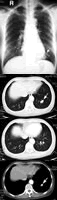

患者,女,54岁。因肉眼无痛血尿1次,左肾肿瘤收入院。术前常规胸部X线检查怀疑左下肺内结节状阴影(图1),为除外肿瘤转移行增强CT检查(图2~7)。

图1 胸部X线平片:左下肺结节状阴影(箭头)

图2、3 胸部CT:肺窗,下肺水平连续层面,示左下肺后基底段结节,向上呈分支状(箭头)

图4 胸部CT:纵隔窗,示结节增强明显(箭头与图2同一水平层面)